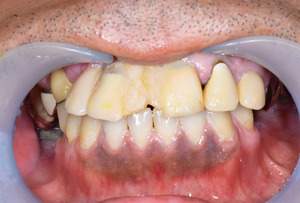

| 年齢・性別 | 63歳・男性 |

|---|---|

| 主訴 | インプラントがしたい |

| 治療内容 | オールオン4(上顎) |

| 治療費 | オペ料金(仮歯・薬代金含み)150万円+上部構造 (ハイブリットセラミック)150万円=計300万円(消費税別) |

| 治療期間 | 7ヶ月 |

| リスク・副作用 | 治療後の口腔管理が不適切な場合、インプラント周囲に炎症が生じインプラントが脱落する恐れがある。 |

審美的にも、機能的にも調和がとれており何よりも食べ物がちゃんとかめると言う事に感激されておりました。

今後定期検診をしながら経過を診て行きたいと思い

ます。